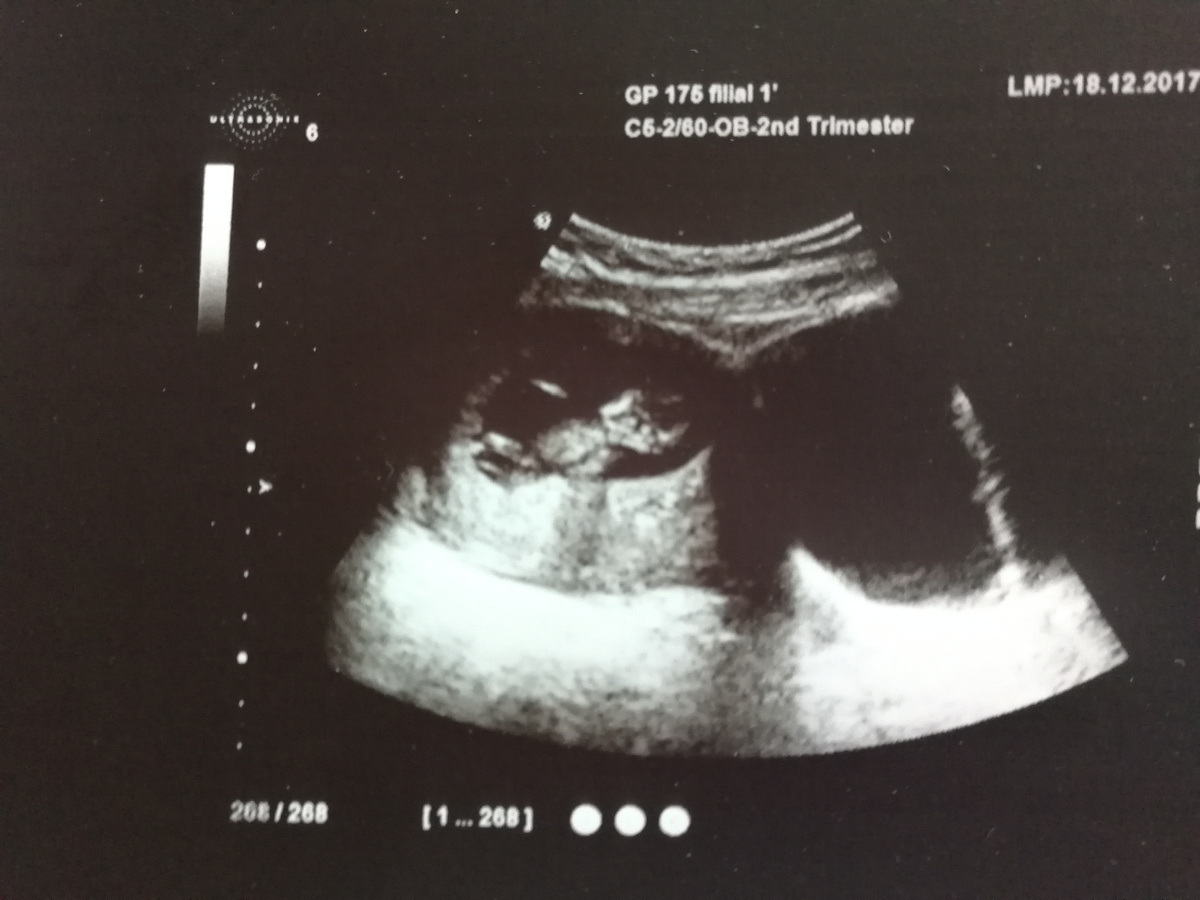

Кстати, при проведении УЗИ в период беременности после 34-35-й недели удается диагностировать ГРУБЫЕ НАРУШЕНИЯ – подвывих и вывих бедра, то есть те изменения, при которых суставная поверхность головки бедра не соответствует поверхности вертлужной впадины таза ребенка. А я как раз и делала УЗИ в 38 недель – в поликлинике, и перед родами на 39-й неделе – в роддоме. И все было в НОРМЕ. Никаких патологий выявлено не было. Только говорили, что ребенок крупный.